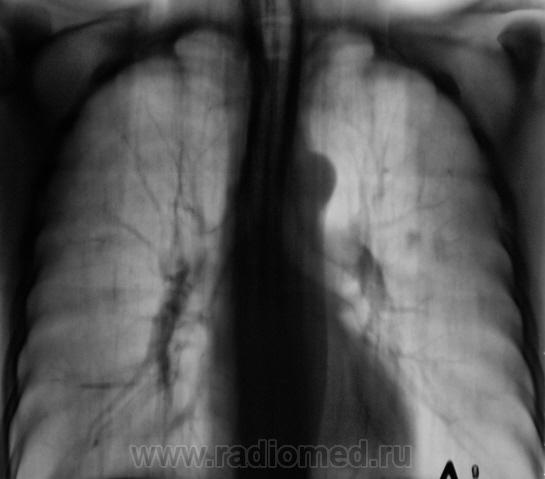

Рентгенограмма.

С двух сторон в верхних долях очаги. На вскидку tbs. А что с клиникой, анализами, анамнез.

Двусторонний очаговый туберкулез.

В s 1 -2 и глубоких отделах s6судя по срезам очаги,справа с включениями кальция,на фоне фоброзно измененного легочного рисунка

Скорее диссеминирмванный так как пораженно более 2-х сегментов.

Такое ощущение, что он свой ТБС уже пережил, возможно на ногах. Иногда фтизиатры пользуются термином - самоизлеченный ТБС ( возможно чуть по другому). А вот те тенюшки в левом легком - это то, что может вырасти в дальнейшем в какое-нибудь деонтологическое заболевание. Цепляться ли за них сейчас? Через год будет поздно. Мы такое уже проходили. И что-же делать?